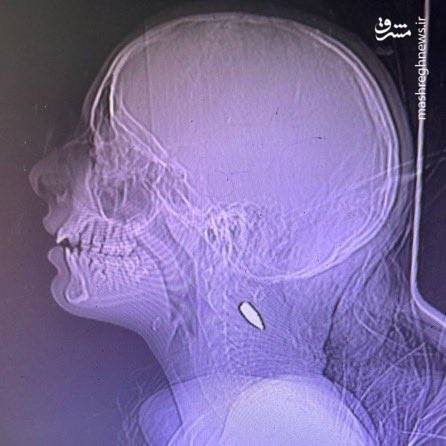

آنان با تصاویر رادیوگرافی از اعدام و شلیک به سر و گردن کودکان با (گلولههای ۵.۵۶ ناتو) مستندات آوردهاند و از کشتار، گرسنگی دادن و گورهای جمعی روایاتی هولناک کردهاند.